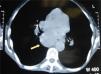

Se realizó una esofagogastroscopia evidenciándose una masa que estenosaba el tercio inferior del esófago. El estudio histológico de esta lesión esofágica evidenció un carcinoma epidermoide. Asimismo la tomografía axial computarizada toracoabdominal mostró adenopatías en el receso pleuro-acigoesofágico y subcarinales (fig. 4).